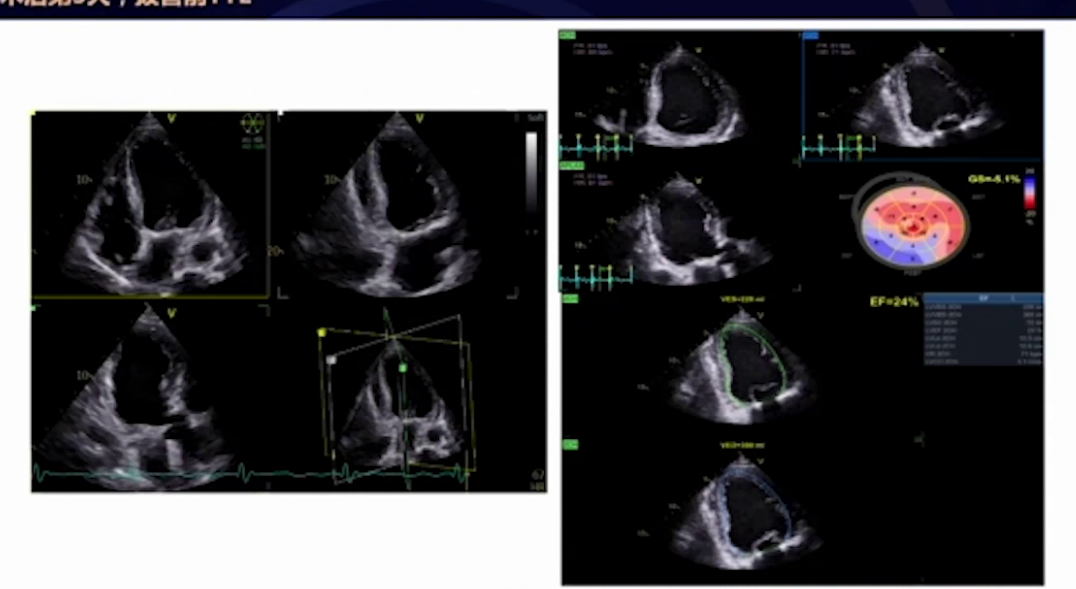

超声心动图:LVEF值低,左室流出道内径增大,主动脉瓣存在狭窄及反流,二尖瓣关闭不全,外院冠脉CAG提示前降支供血区域缺血,右冠远端100%闭塞。

静息心肌灌注SPECT+心肌代谢PET/CT:提示左心室心腔增大,整体收缩功能严重受损。

入院5天复查超声心动图:左心仍增大,EF值有所上升,但主动脉瓣及二尖瓣病变情况仍较严重。

3.术后后期:术后第4天安返病房,记录此时生命体征及用药情况。术后第7天乳酸值先升高后下降,患者病情稳定,无胸闷胸痛等不适,复查经胸超声EF值升至30%,人工生物瓣功能正常,二尖瓣未见反流,随后出院。4月30日电话随访患者情况满意。

在术后管理阶段,预防恶性心律失常成为重点。患者术后未能恢复有效的窦性心律,持续为房颤并偶发室上性心动过速,伴随循环波动,仍处于高危状态。然而,经过综合干预,患者最终预后良好。随访数据显示,其心功能得到明显改善,经胸超声心动图提示射血分数上升至30%,左室收缩末期容积从80ml降至68ml,这证实了整个围术期干预方案的有效性。